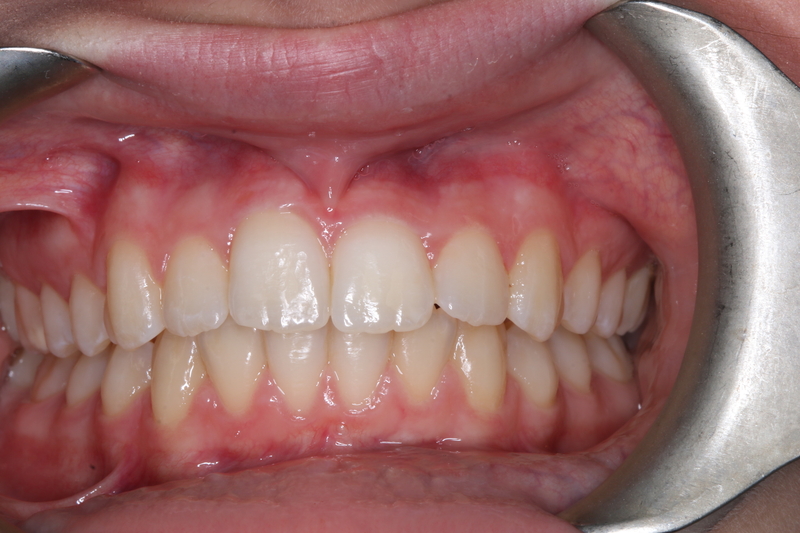

Case 5 – Dental Trauma

Severe Intrusion during braces